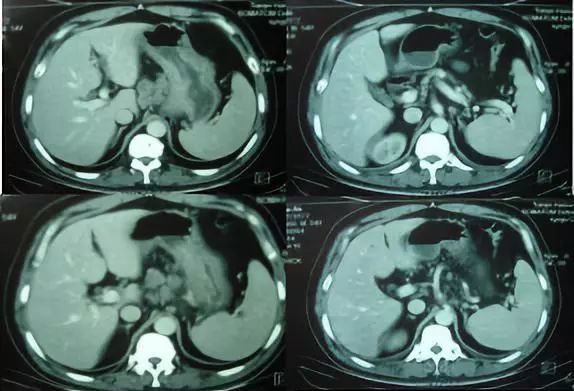

胃镜:进镜40cm见息肉样病变延及贲门及胃底、胃体,胃腔狭窄,尚能通过镜身,胃体中部近半周弥漫性粘膜破坏区,咬检病理(胃底)中分化腺癌,(贲门)粘膜急慢性炎症,腺体重度不典型增生,于炎性渗出及坏死组织中见异型细胞巢;HER2过表达,IHC 3+。肿标:CA199 742U/ml;CEA 78U/ml。胸腹盆CT:贲门胃底胃壁及胃体上部胃壁不规则增厚;下纵膈贲门周围肝胃韧带区及腹膜后多发肿大淋巴结;腹盆腔少量积液。

▲胸腹盆增强CT(2014.09.02)

小结:中年男性,探查术后患者,晚期胃癌诊断明确,肝门区,腹膜后多发转移。讨论目的:制定进一步治疗方案。

影像科:从目前CT考虑,贲门部肿瘤累及胃底胃壁,伴腹腔多发转移,分期明确。